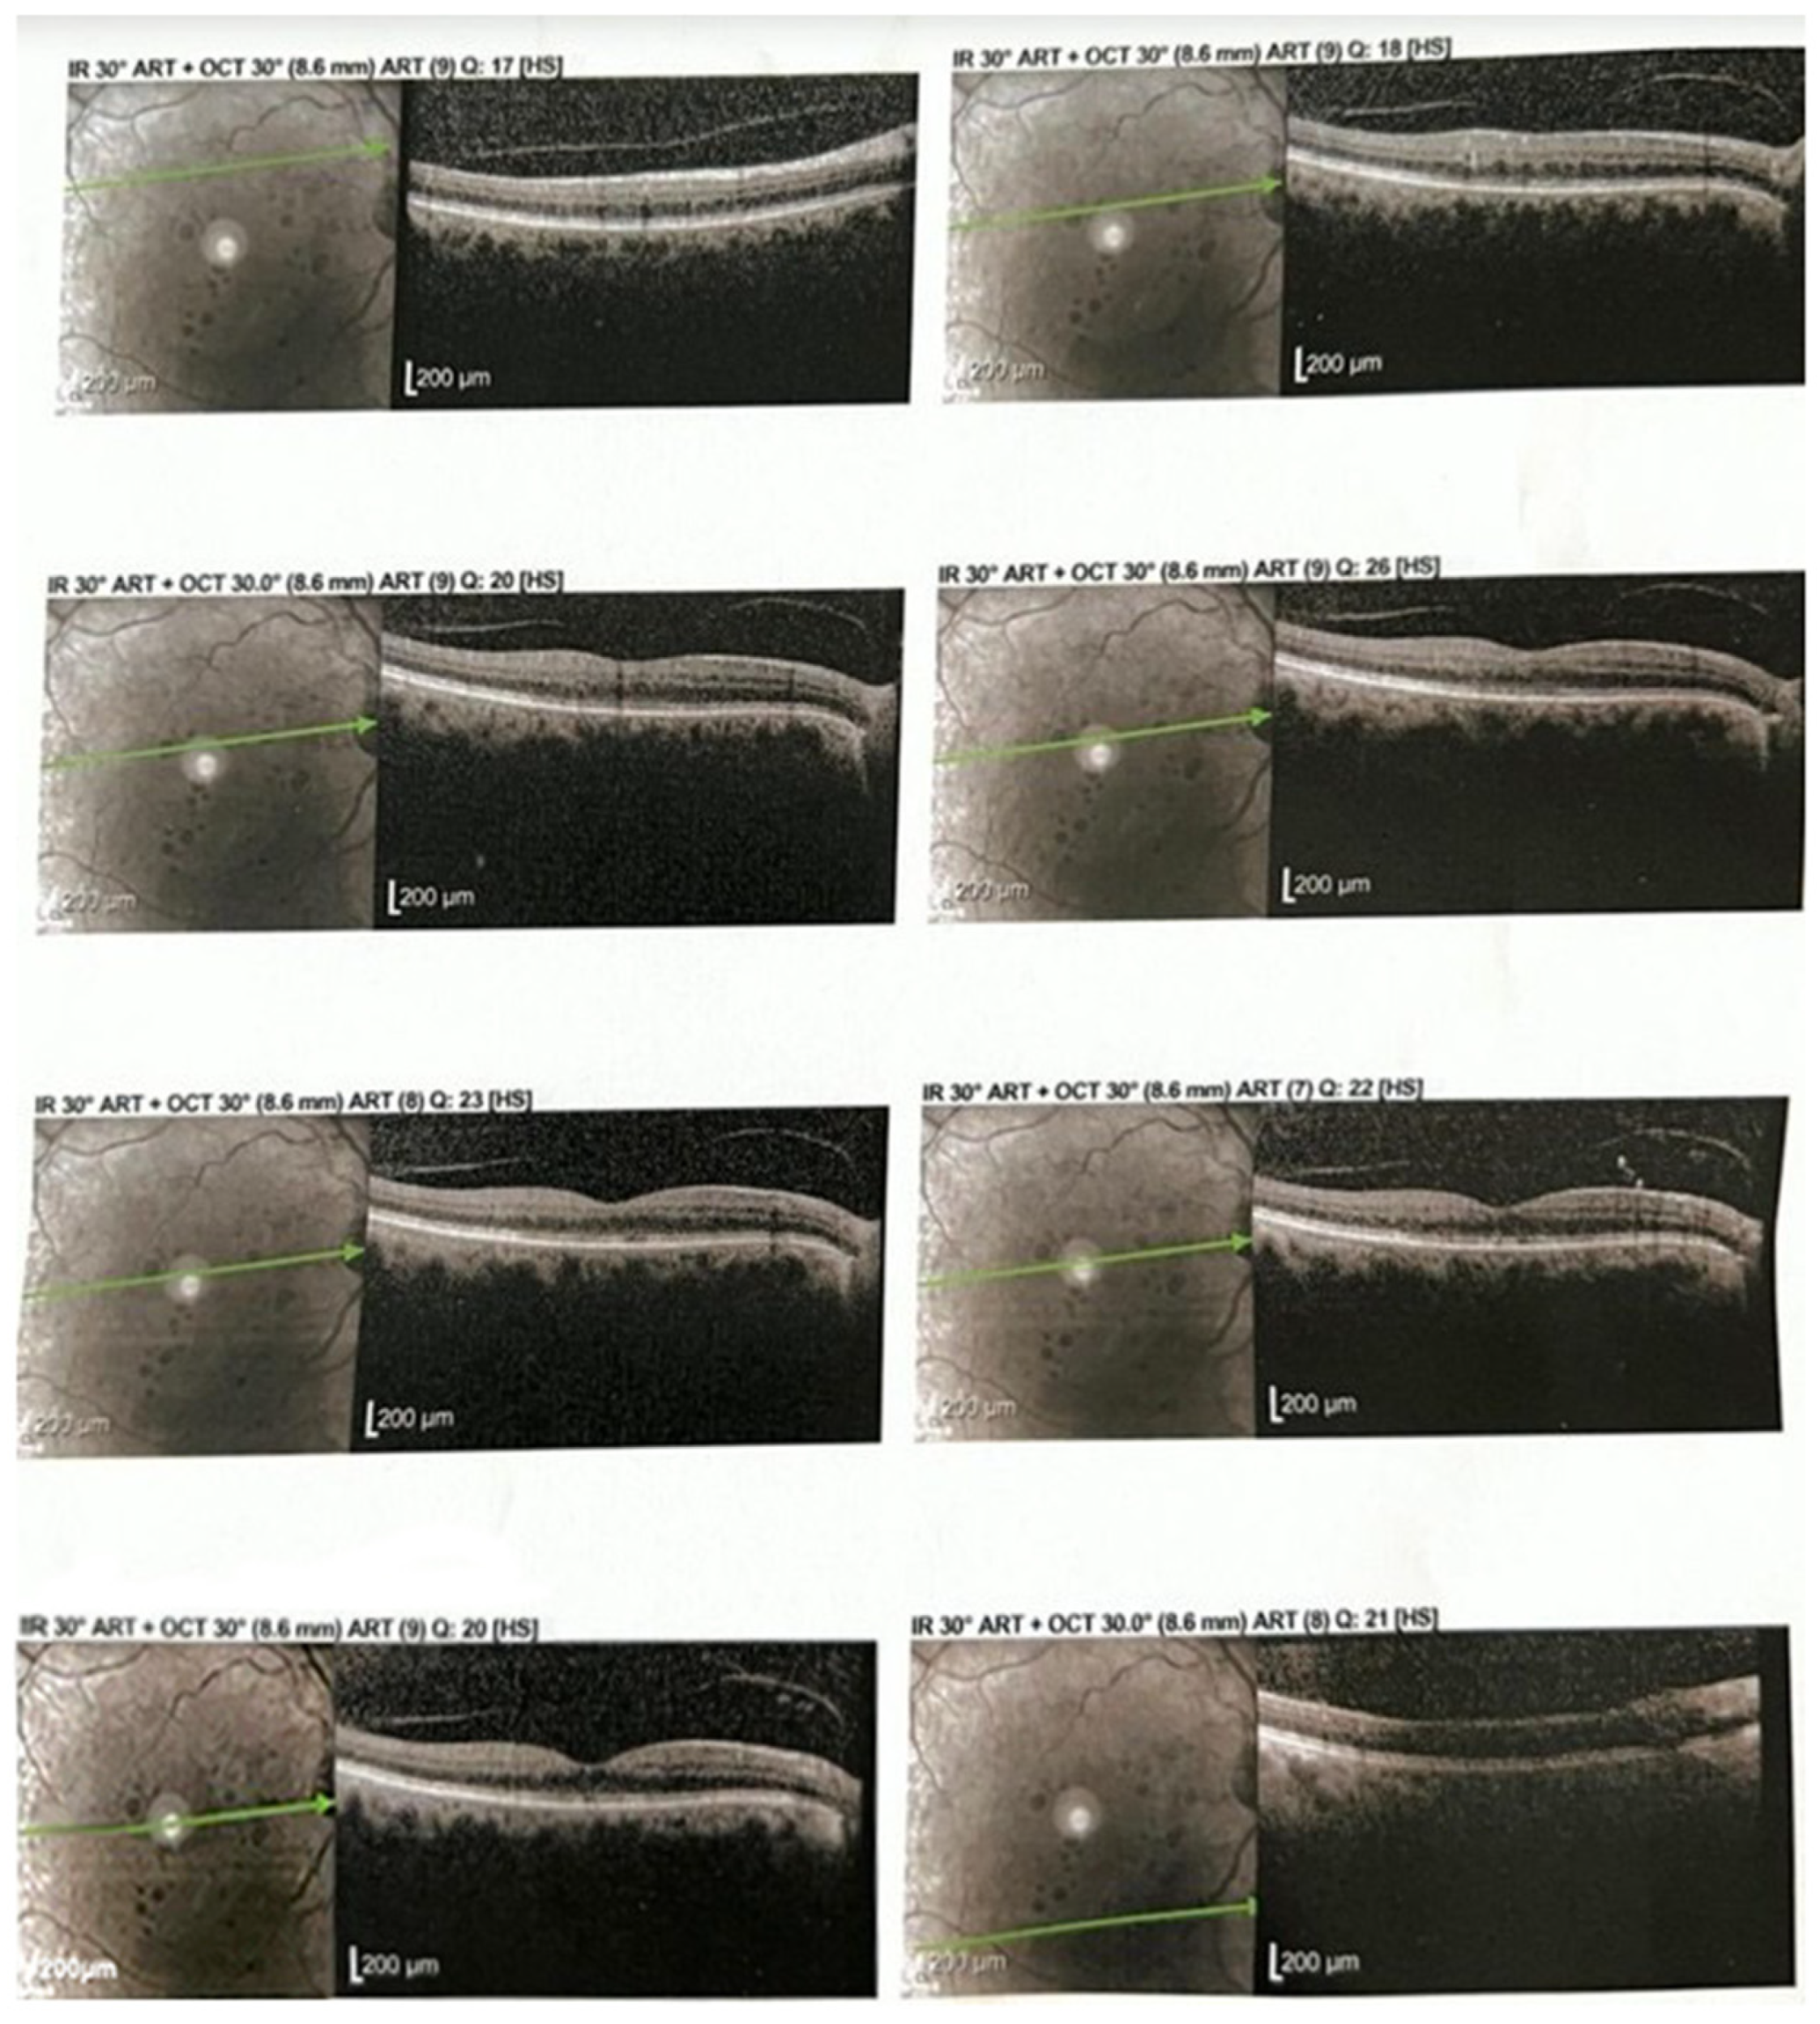

2.4. Figures